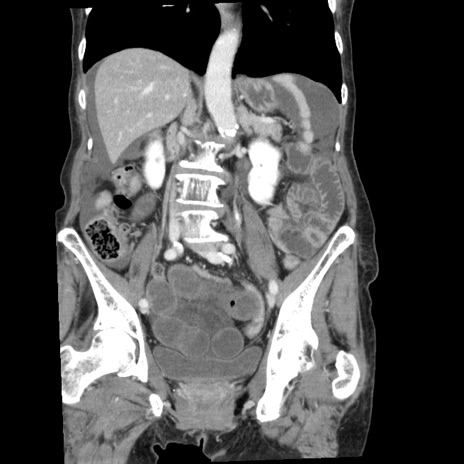

症例1(冠状断像)

【症例】80歳代女性

【主訴】腹痛

【現病歴】8時間前から腹痛あり来院。

【既往歴】糖尿病、脂質異常症、子宮体癌にて子宮全摘術

【身体所見】意識清明・会話良好だが腹痛で苦悶様、全腹部にわたって反跳痛と圧痛あり

【データ】WBC 13600、CRP 0.14、LDH 224、CK 90